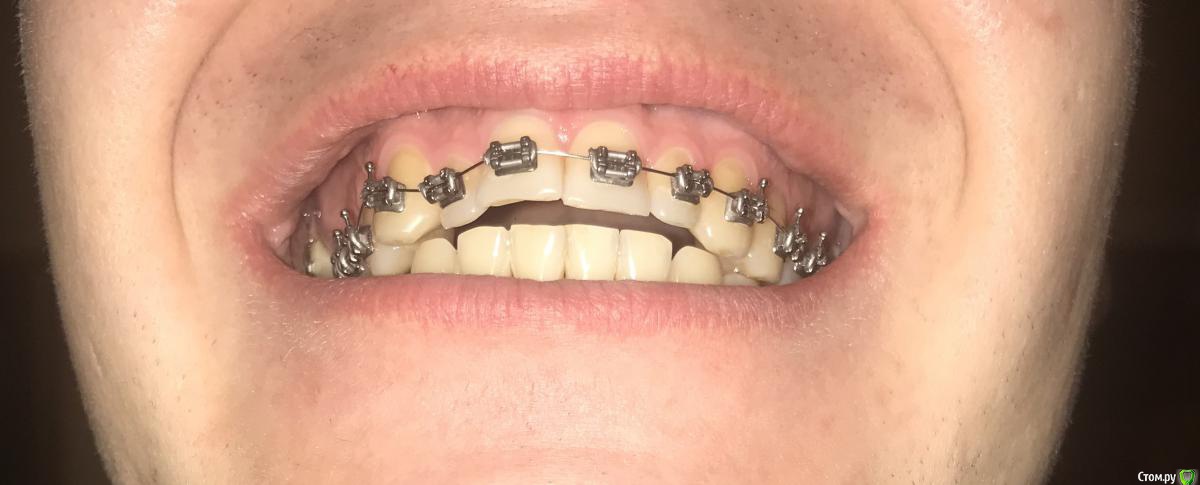

Ситуация такая, что начал лечение у ортодонта, но как оказалось, сильно исправлять прикус он не будет, только выравнивание зубного ряда. Расстояние выноса верхних зубов вперед в ширину четверки, но удалять четверки мне бы не хотелось. Так же, есть смещение в бок. Есть одна коронка и одна вкладка, много зубных каналов запломбировано. В целом, сильных проблем с прикусом я не ощущаю, но не будет ли потом проблем с челюстным суставом? Морально я готов к лечению, хотелось бы все сделать раз и навсегда, но с чего начать, какими способами нужно будет все исправлять? Придется ли делать операцию на челюсти или как то выносить нижнюю челюсть вперед другими способами? Нужно ли удалять восьмерки(осталась пара)?

И самое главное, необходимо найти грамотного специалиста и клинику, очень не хотелось бы иметь какие то проблемы со здоровьем после всех изменений, а так же бесконечного перелечивания, как у некоторых. Мне 31. Буду благодарен, если кто посоветует врача, желательно по собственному опыту или по хорошим отзывам в городе Москва, южная часть Подмосковья.